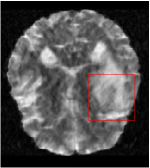

Qualitative comparison between conventional and Meta-learning methods are shown in Figure 1 and 3, which display the reconstructed MR images of the same slice for T1 and T2 respectively, we label the zoomed-in details of HGG in the red boxes. We observe the evidence that conventional learning is more blurry and lost sharp edges, especially in lower CS ratios. From the point-wise error map, we find meta-learning has the ability to reduce noises especially in some detailed and complicated regions comparing to conventional learning.

In this section, we test the generalizability of the proposed model that tests on unseen tasks. We fix the well-trained task-invariant parameter and only train for sampling ratios 15%, 25% and 35% with radio masks and sampling ratios 10%, 20%, 30% and 40% with Cartesian masks. In this experiment, we only used 100 training data for each CS ratio and apply a total of 50 epochs. The averaged evaluation values and standard deviations are listed in Table 5.4 and 5.4 for reconstructed T1 and T2 brain images respectively that proceed with radio masks, and Table 5.4 shows the qualitative performance for reconstructed T2 brain image that applied random Cartesian sampling masks. In T1 image reconstruction results, meta-learning improved 1.6921 dB in PSNR for 15% CS ratio, 1.6608 dB for 25% CS ratio, and 0.5764 dB for 35% comparing to the conventional method, which in the tendency that the level of reconstruction quality for lower CS ratios improved more than higher CS ratios. A similar trend happens in T2 reconstruction results with different sampling masks. The qualitative comparisons are illustrated in Figure 2, 4 and 5 for T1 and T2 images tested in skewed CS ratios in radio masks, and T2 images tested in Cartesian masks with regular CS ratios respectively. In the experiments that conducted with radio masks, meta-learning is superior to conventional learning especially at CS ratio 15%, one can observe that the detailed region in red boxes keeps edges and is more close to the true image, while conventional method reconstructions are hazier and lost details in some complicated tissue. The point-wise error map also indicates that Meta-learning has the ability to suppress noises.